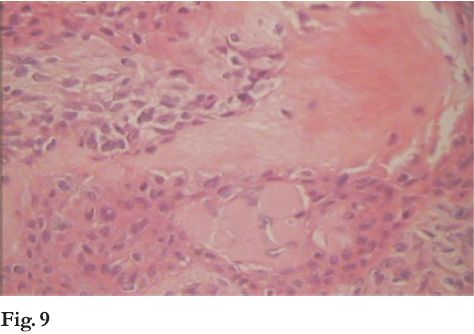

Paciente de 6 años de edad, sexo femenino, raza blanca que concurre a la Clínica de Estomatología en marzo de 2007 derivada de Policlínica Municipal, por una lesión gingival indolora, en la zona ántero-superior izquierda, de tres años de evolución.

Fue tratada con antibióticos en varias ocasiones y finalmente se realizó la exodoncia de la pieza 6.1 en estrecha relación con la lesión.

Ésta continuó su crecimiento hasta llegar a los 2 cm de diámetro en sentido mesio-distal y a los 2,5 cm de diámetro vestíbulo-palatino. De crecimiento lento provocó el desplazamiento de la pieza 6.2.

Al examen clínico se presenta como una tumefacción gingival circunscripta, sesil, cubierta por mucosa normal con la impronta de las piezas inferiores que contactan en oclusión. (fig. 1 y 2).

Con el diagnóstico clínico de hiperplasia fibrosa reactiva se realiza biopsia incisional. Histopatológicamente correspondió a una lesión fibromatosa benigna, de histogénesis odontogénica (fig. 3).